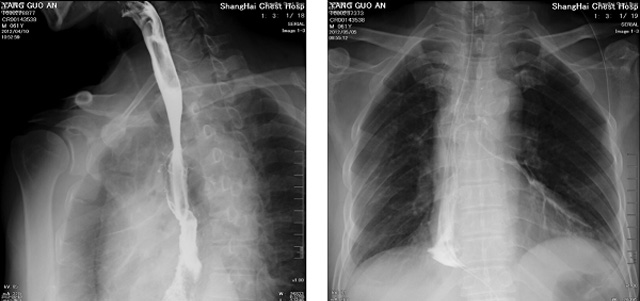

DR设备在2020年的新冠疫情中,加速了市场调整。以医院为主的向二三级市场转变。特别是小巧灵活的移动DR设计,填补CT和磁共振不能三维检查的缺点,满足内科外科特别是骨科的影像诊断需求。还有悬吊DR设备CT断层射线系统。使用锥束成像技术对整个脊柱和整个下肢进行了体积三维扫描。无需使用对比剂,即可使用X射线呼吸功能标测来模拟模拟气流和血流,以评估患者的肺动脉血栓。

数字化X线摄影依然是患者初筛的关键一环。静态DR限制于探测器平台。只能进行简单普通的数字化影像检查。胸部的疾病没办法筛查出微小的病灶。这样导致DR慢慢的被CT跟磁共振代替。这样造成了原来配套的数字化影像DR设备的 闲置。所以DR需要跟CT融合扩大DR的检查使用场景。为DR提高更多的市场价值。X射线技术的原始形式和面向未来的可能性打破了CT成像和DR成像扫描技术之间的限制。融合成像趋势更加明显,多峰成像趋势发展更加迅速。